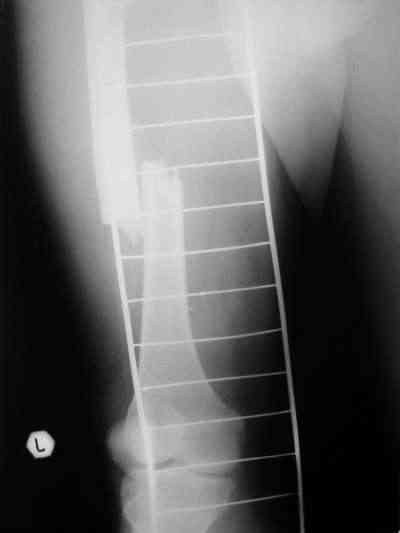

Около 10 дней назад выполнил остеосинтез бедренной кости LC-DCP и DHS по поводу фрагментарного оскольчатого перелома в средней трети и чрезвертельного перелома.

Снимки в приложении.

В приложении и имеющийся в наличии брейс. Приношу извинения за низкое качество снимков.

Качество снимков приемлемое. С нагрузкой категорически не надо спешить - только при уверенных рентгенологических признаках сращения на обоих уровнях в данном случае. Т.е. не только на диафизе, но и в вертельной области. При безупречном синтезе DHS ранняя нагрузка в этой зоне была бы безопасна, все определялось бы сращением диафиза. А поскольку винт в DHS сделали ну о-очень короткий, то ойкнуть не успеете, как

проксимальный отдел бедра в варус кувыркнется.